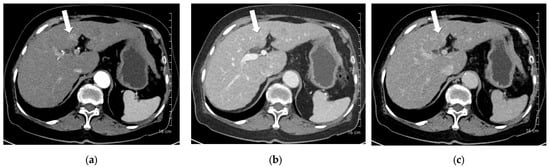

Figure 4. A 55-year-old man with hepatocellular carcinoma (HCC) on magnetic resonance imaging, characterized by diffusion restriction, high signal intensity on T2-weighted images, and washout. CT was performed using high-concentration iodine contrast material (total iodine dose, 584.14 mg I/kg). Overall image quality in the arterial and portal phases was acceptable. (a) A 7-mm enhancing nodule (arrow) is visible on the arterial phase at 100 kVp; (b,c) The nodule is inconspicuous on the portal and delayed phases. Both reviewers classified the lesion as benign (LI-RADS category 3).